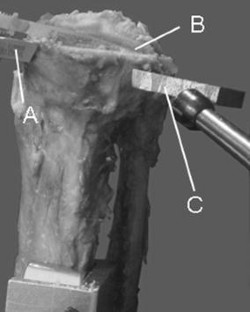

Tibial components of the Oxford Uni were implanted in six paired fresh-frozen tibiae with a defined extended saw cut (10°) at the dorsal cortex of each specimen. In one set, surgery was performed with cement fixation, and in the other, cementless components were implanted. Vertical loads were then applied under standardised conditions to fracture the specimens.

Fig. 2